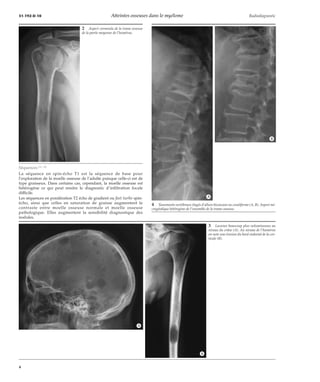

La séquence en spin-écho T1 est la séquence de base pour

l’exploration de la moelle osseuse de l’adulte puisque celle-ci est de

type graisseux. Dans certains cas, cependant, la moelle osseuse est

hétérogène ce qui peut rendre le diagnostic d’infiltration focale

difficile.

Les séquences en pondération T2 écho de gradient ou fast turbo spin-écho,

ainsi que celles en saturation de graisse augmentent le

contraste entre moelle osseuse normale et moelle osseuse

pathologique. Elles augmentent la sensibilité diagnostique des

nodules.